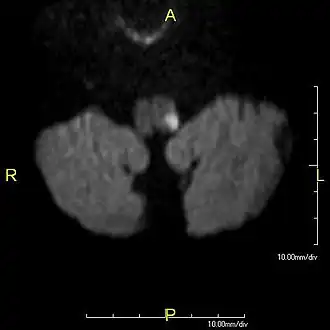

Transversale coupe van een diffusiegewogen MRI-opname van de hersenstam en de kleine hersenen, met een infarct (witte vlek) in de linker dorsale medulla oblongata